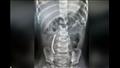

توفي الطفل ويُدعي "ريس ميلوم" عندما التصقت الكرات الفضية ببعضها البعض في أمعائه، مكونة صف طوله 30 مم، ما أدى إلى ثقب أمعائه الدقيقة، ولكن الطفل لم يُخبر أحدا بابتلاعه للمغناطيسات، حتى بعد شعوره بالتعب والألم، واُكتشف هذا الأمر خلال فحص الأشعة المقطعية لكامل الجسم بعد وفاته.